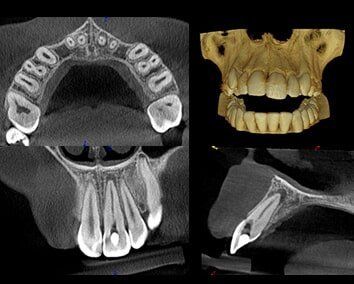

ROOT CANAL THERAPY

When a tooth breaks, cracks or has constant pain, treatment often involves removing an infected nerve. Other symptoms may include the inability to chew on a tooth, thermal (hot-cold) sensitivity, or swelling beside a tooth. Once the nerve is removed and thermos plastic/bioceramic sealer is used to fill the space left.